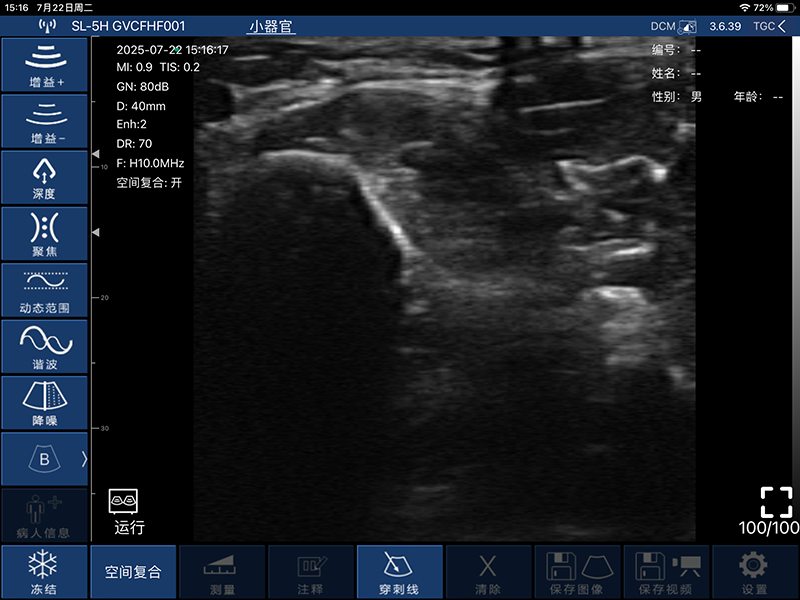

带指套探头的掌上彩超,小小的掌超主机放在口袋可随处走,手指套着探头即可完成打图成像,让手不再需要握着探头而可解放出来还能拿其他东西,特别适合术中等应用

- 穿刺辅助功能:平面内穿刺引导线功能,平面外穿刺引导与血管自动测量功能